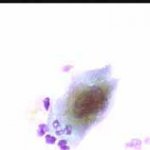

Περιστατικό ασθενούς που παρακολουθείται στο ιατρείο μας από το 1993, τότε ηλικίας 37 ετών, αρχικά λόγω ασυμπατωματικού κυτταρολογικά εμμένοντας έρπητος τραχήλου της μήτρας. Το γεγονός αυτό μας οδήγησε στην διερεύνηση της περιπτώσεως. Η ασθενής επασχε από A.I.D.S.

Είχαμε την ευκαρία να παρακολουθήσουμε ανά 6μηνο γυναικολογικά, κολποσκοιπικά και κυτταρολογικά την γυναίκα από το 1993 μεχρι και το 2008. Από τις εξετασεις αυτές, παρουσιάζουμε χαρακτηριστικές κυτταρολογικές εικόνες . Όι παρακάτω κυτταρολογικές εικονες προέρχονται από την 2η κατά σειρά εξέταση της ασθενούς το 1993. Οι κυτταρολογικές αλλοιώσεις ερπητος συνεχίζουν να υφίστανται.

Ακολουθουν κυτταρολογικές εικονες από τα έτη 1997 - 1998.